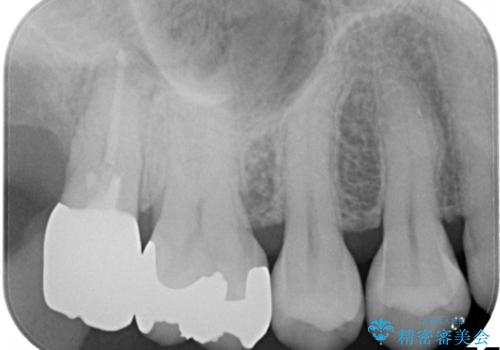

- 虫歯の治療を希望され来院された患者様です。

根管治療を行いオールセラミッククラウンによる治療を行いました。(根管治療は林先生に依頼)

歯肉の下にも虫歯が広がっており歯周外科を行った後、被せもの治療を行いました。